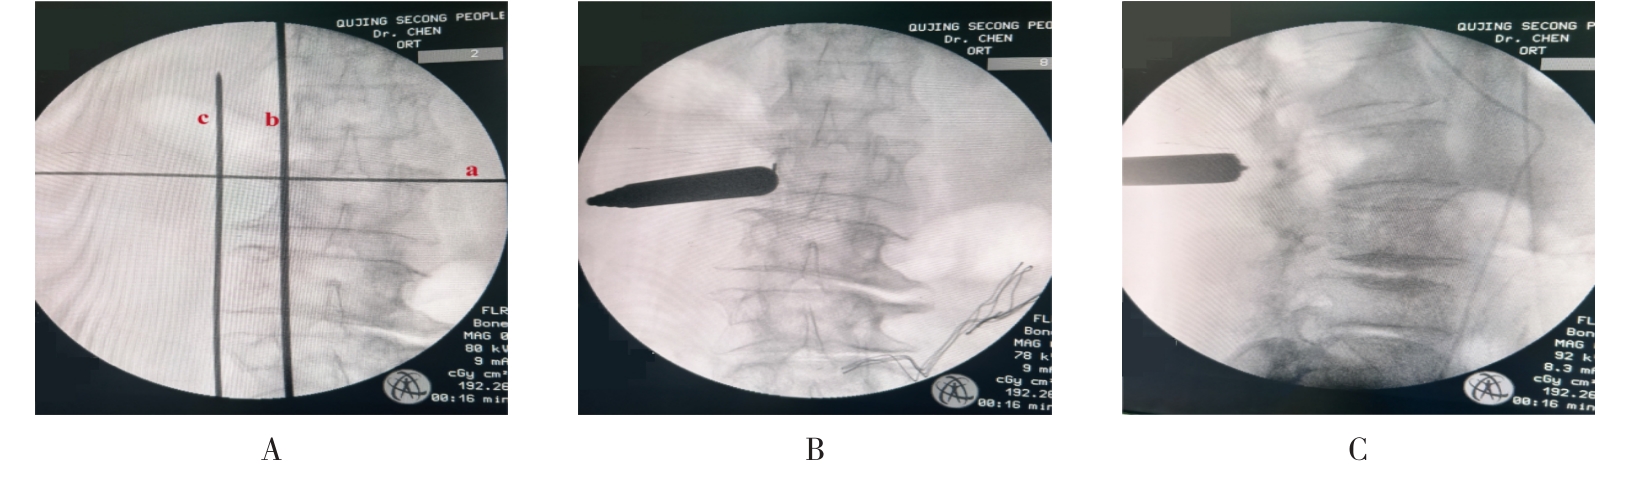

• 单通道非同轴脊柱内镜经椎间孔外入路(椎板外切迹)治疗极外侧椎间盘突出症的临床疗效观察

2026, 32(3):28-36. DOI: 10.12235/E20250050

摘要 (43) HTML (65) PDF 6.88 M (47) 评论 (0) 收藏

摘要:目的 观察单通道非同轴脊柱内镜经椎间孔外入路(椎板外切迹)治疗极外侧椎间盘突出症(FLLDH)的临床疗效。方法 回顾性分析2022年5月-2024年5月该院收治的,行单通道非同轴脊柱内镜经椎间孔外入路(椎板外切迹)治疗的FLLDH患者70例。于术前和术后,评估腰腿疼痛程度、腰椎功能和临床疗效。结果 相较于术前,术后3 d和3个月,患者下肢视觉模拟评分法(VAS)评分、腰部VAS评分、Oswestry功能障碍指数(ODI)、数字分级评分法(NRS)评分和Roland-Morris功能障碍问卷(RMDQ)评分明显降低,日本骨科协会(JOA)评分明显升高,差异均有统计学意义(P < 0.05);改良MacNab评分标准显示,末次随访时的优良率为94.28%。结论 单通道非同轴脊柱内镜经椎间孔外入路(椎板外切迹)治疗FLLDH,能明显改善患者腰腿疼痛和腰椎下肢功能,其具有创伤小、易操作、安全性高和疗效好等优点,值得在临床推广应用。